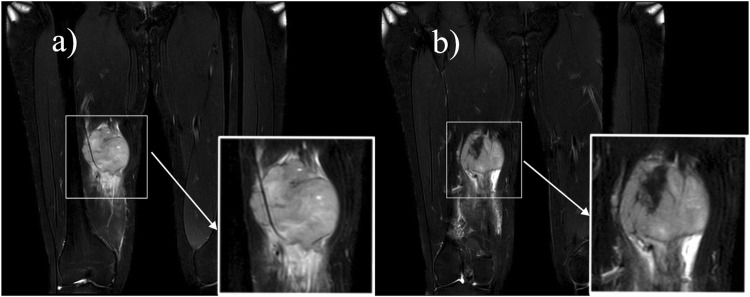

Synovial sarcoma (SS) is a rare and malignant mesenchymal neoplasm. We report a case of a 16-year-old Chinese female diagnosed with biphasic synovial sarcoma. The imaging features, surgical procedures and pathological results of the lesion were described in detail. Additionally, we conducted a review of the literature on synovial sarcoma of the thigh over the past 2 decades, identifying a total of 25 relevant case reports and summarizing the characteristics of these cases. Synovial sarcoma has a high degree of malignancy, with a high recurrence and metastasis rate, and a 5-year survival rate of 36%-76% and a 10-year survival rate of 20%-63%, so early detection of the lesion and preoperative differential diagnosis are of paramount importance in the treatment of patients.